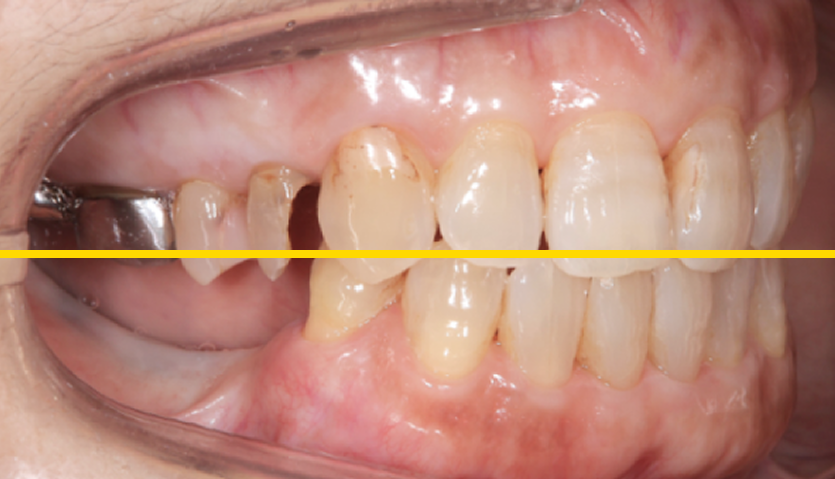

診査していくと、入れ歯の強度の問題ではなく、この方の噛み合わせに問題がある、「病的咬合」であると診断しました。

話を聞くと、この患者さまの場合、40代くらいから入れ歯を使用されていたそうです。何故早期に歯がなくなってしまったのか、また、入れ歯の破折を繰り返すのか、この原因は今残っている、下の前歯の傾きにあると判断しました。

前歯の役割を「アンテリアガイダンス」と呼びます。この「アンテリアガイダンス」が不適切だと、奥歯の負担が大きくなります。この患者さまの場合その負担に奥歯の周囲組織が耐えきれず、早期に抜歯に至ったようです。また、奥歯がなくなると上の前歯は下の前歯に突き上げられ、強い力が加わり揺れたり、割れたりします。 このような理由で口腔全体を含めた「全顎の治療」計画を提案させていただきました。

最後は下の前歯だけが残る、この状態の患者さまはよく見かけます。この患者さまの場合、歯がなくなった原因が「不適切なアンテリアガイダンス」です、これを改善しない限り、入れ歯にしろ、インプラントで歯を作るにしろ、ご自身の歯が抜けてしまったように壊れてしまうのは当然です。

まず一番必要なのは、下の前歯の傾きを適正なものにし、「適切なアンテリアガイダンス」を作ることです。今回、下の前歯を全て残した状態で矯正治療により適切な位置に歯を動かすか検討しましたが、歯を支える骨の問題で矯正治療では対応できず、犬歯以外は抜歯し、ブリッジと言う橋渡しの歯にすることで適切な前歯の形を作る治療計画を立てました。

理想は歯も残して病的な位置を改善させたいのですが、今回は残念ながら無理でした。ただ、病的な位置をそのままにすることで安定した状態が作れません。歯より「安定して噛める状態」を優先するか、病的な位置の歯を残し、安定を求めずに治療を繰り返しながら過ごすのか、これは患者さまとの相談のうえ決定するようにしております。

今回は抜歯し「安定して噛める状態」を作ることで同意されたのでこのような治療を行なっております。下の歯は入れ歯より強固なインプラントを選択し、上は総義歯を使用し治療をいたしました。